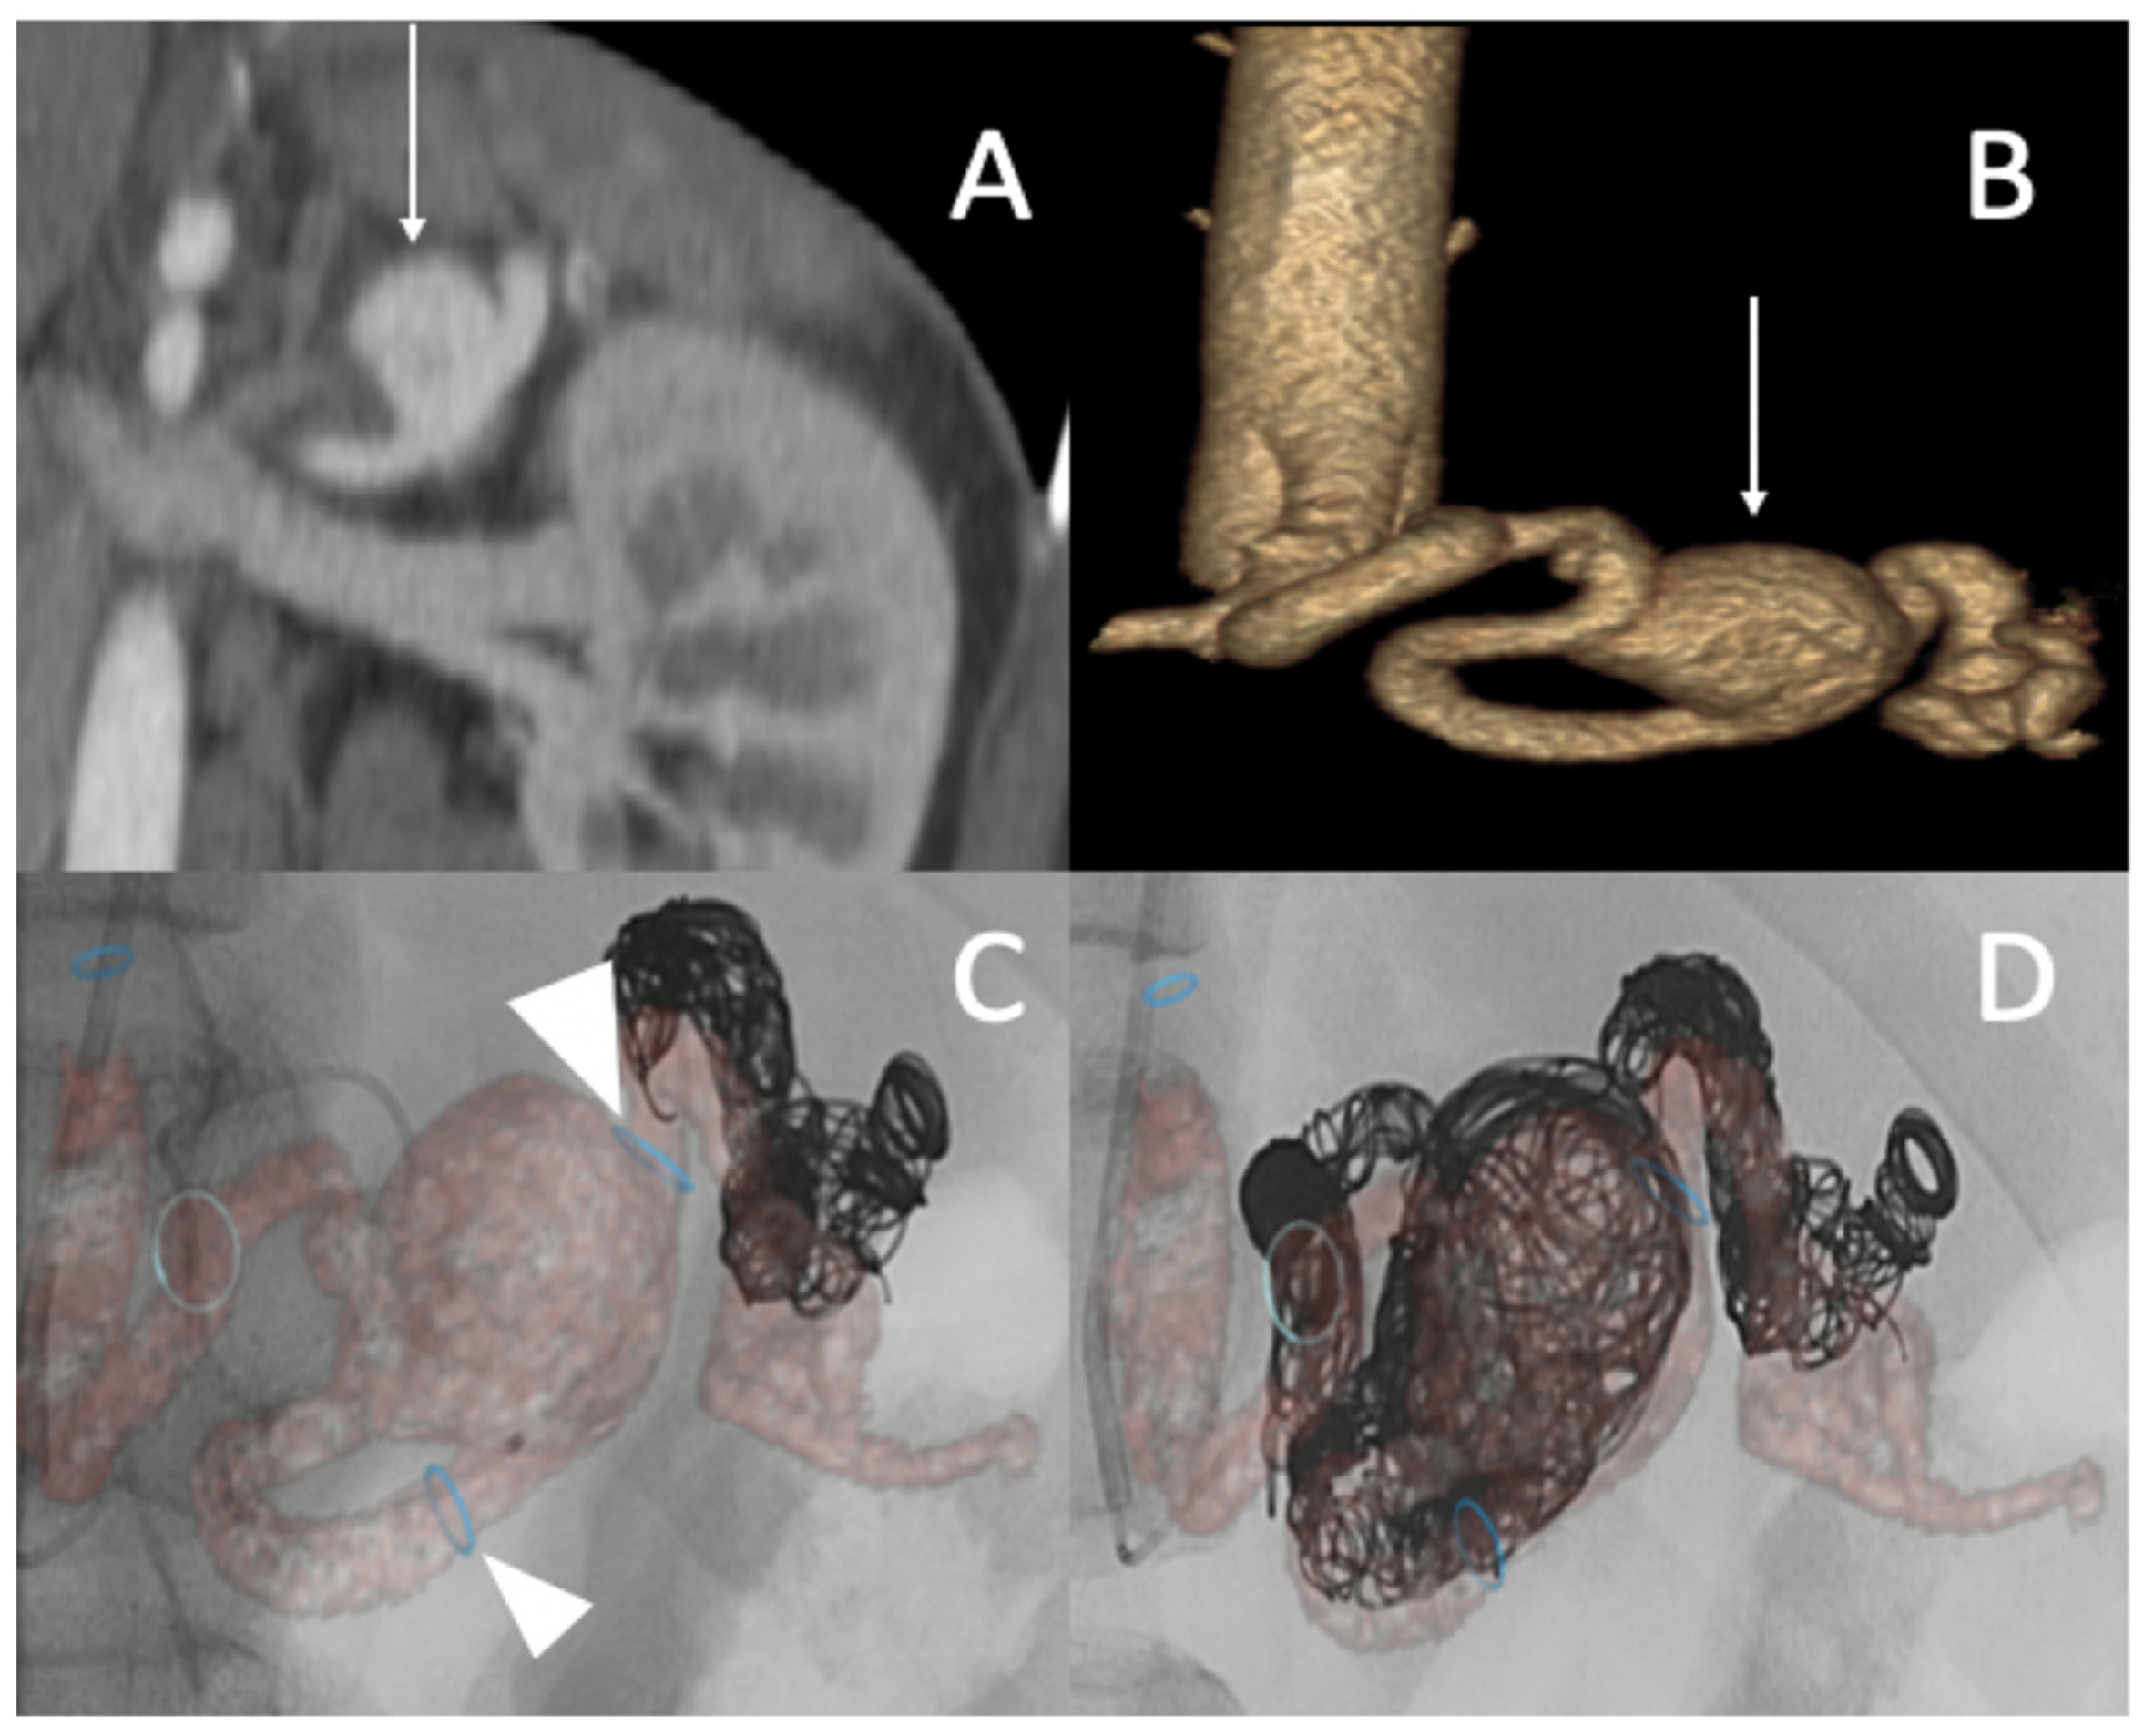

A 25-year-old male patient, with a familial history aortic rupture leading to the sudden death of his father in 1999, was referred to our hospital after the appearance of a left groin hematoma. An enhanced abdominal and pelvic CT scan revealed an aneurysm of the splenic artery measuring 30 × 25 mm and a recent dissection of the left common iliac artery, with a maximum iliac diameter of 12 mm (Figure 3A,B). In his medical history, he complained of abdominal pain within the left hypochondrium for the past 8 months following physical exercise. After a multidisciplinary evaluation, we first decided to embolize the splenic aneurysm using coils to prevent the risk of rupture. Under general anesthesia, a 6 F introducer was inserted into the left humeral artery using the Seldinger technique. Two-dimensional/three-dimensional fusion with preoperative CT angiography was performed to guide the catheter and microcatheter for the more rapid catheterization of the aneurysm and to decrease the radiation exposure (Figure 3C). We catheterized the celiac trunk artery using a 6 F ENVOY catheter (Codman-USA) and then catheterized the aneurysm using a Progreat 2.8 F microcatheter (Terumo-Tokyo, Japan). We started to exclude the outflow of the aneurysm with several Ruby coils (Penumbra-Alameda, CA, USA). We then filled the aneurysm with multiple coils starting with a 3D Ruby standard coil of 34 mm diameter and after decreasing the diameter of the coils using interlock detachable coils (IDCs, Boston Scientific, Marlborough, MA, USA), Nester coils (COOK 6 USA), and packing coils (Penumbra-Alameda, CA, USA), and we occluded the aneurysm inflow using Ruby standard coils (Penumbra-Alameda, CA, USA) (Figure 3D).

Figure 3.

(A,B) Abdominal CT angiogram with 3D image and arteriography with image fusion (C,D) showing the aneurysm in the splenic artery (arrows). We marked the proximal and distal extremities of the neck of the aneurysm (head arrow), and then we started the embolization using multiple coils after, within, and before the aneurysm.

Successive CT scan follow-up revealed rapid aneurysmal growth of his left common iliac artery with a 12 mm increase in diameter within one week. The patient complained of left groin pain. A hybrid surgical treatment of left iliofemoral bypass and endovascular exclusion of the internal iliac artery was selected (Figure 4).

Figure 4.

(A) Abdominal CT angiogram with 3D image showing the dissection of the left common iliac artery (arrow); (B) arteriography shows the left iliofemoral bypass (star) and dissection of the left common iliac artery (arrow); (C) occlusion of the left internal and external iliac arteries by coils and then a plug (head arrow); (D) arteriography final shows the permeability of left iliofemoral bypass (star).